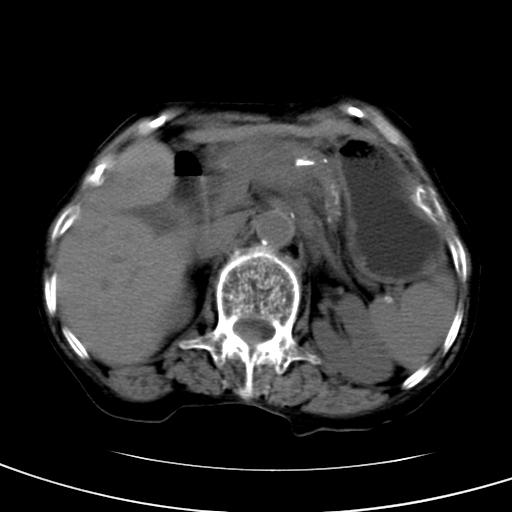

以下是引用wolft在2008-3-5 12:30:00的发言:[br]肝脏未见明显肿块影,但肝左叶增大,跨越腹中线到达脾胃前,且有一血管过去,考虑为先天变异:獭尾肝,胆囊为慢性胆囊炎急发,但胰腺头颈部有增大,密度不均匀,应该ct增强一下。

以下是引用zjzjr在2008-3-5 16:41:00的发言:[br]1.考虑慢性胰腺炎急性发作,建议增强除外占位性病变.[br]2.胆囊结石伴胆囊炎.[br]3.肝内胆管结石.